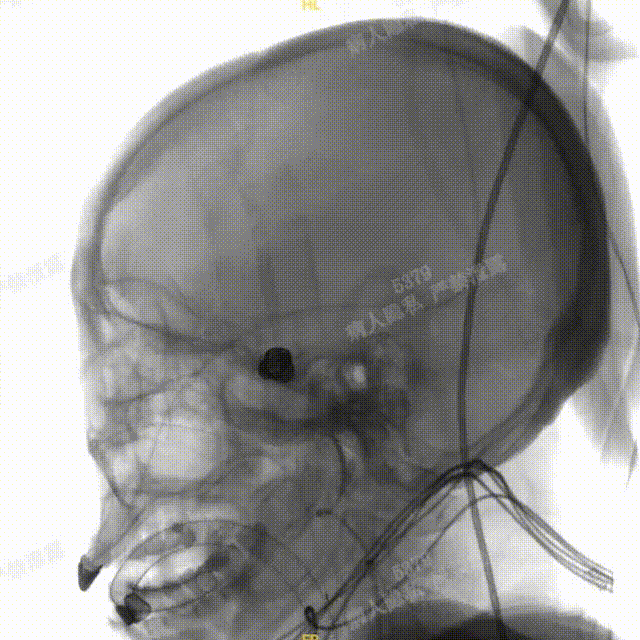

术中DSA造影:左侧颈内动脉正、侧位及3D造影,显示左侧颈内动脉后交通段动脉瘤。

术中DSA造影:右侧颈总动脉3D造影及右侧锁骨下正位造影。

Headway™ 27 156cm微导管内输送FRED 4518血流导向密网支架,系统远端精准定位于预计着陆区以远3-5mm,回撤微导管原位释放支架,头端锚定在颈内末端处。

正位

①输送导丝头端

②支架远端扩口显影点

③有效段起始点

④支架近端扩口显影点

确认支架远端定位于计划位置,预估近端可完全覆盖动脉瘤颈,且锚定距离充足。继续平衡释放系统,确保支架整体充分打开且贴壁良好后,解脱支架。

工作角度

①支架远端扩口显影点

②有效段螺旋显影丝

③支架近端扩口显影点